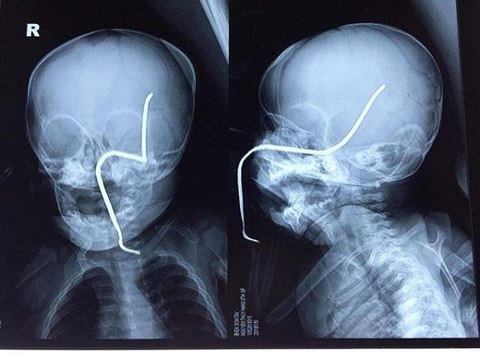

Bé gái 8 tháng tuổi đang chơi bị thanh sắt đâm xuyên sọ

Xã hội - 02/05/2018 21:27

Trong lúc đang chơi gần nhà, một bé gái 8 tháng tuổi ở Thị xã Sơn Tây, Hà Nội bất ngờ bị chiếc máy đang...